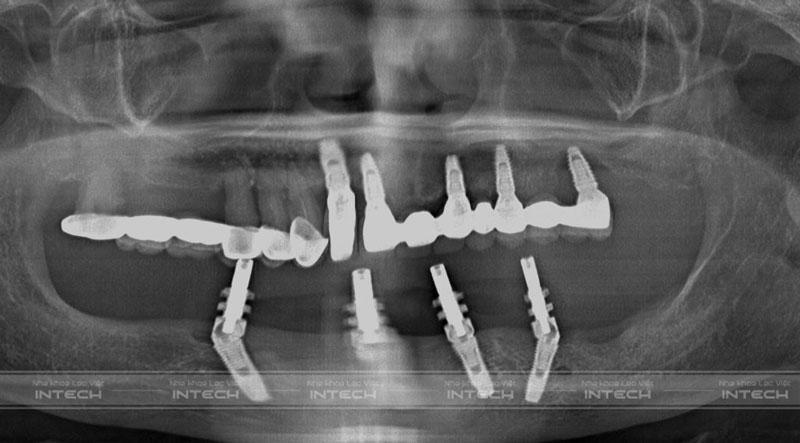

Quá trình cắm implant cho bác Nguyễn Thị Minh Phương diễn ra đúng với kế hoạch điều trị ban đầu của bác sĩ đưa ra. Trụ Implant sau khi cấy đã tích hợp ổn định trong xương hàm. Vị trí các trụ Implant được phân bổ đều, giúp nâng đỡ hàm giả vững chắc, khách hàng có thể thoải mái ăn nhai.

Ảnh phim chụp X-quang của bác Phương sau trồng răng All On 4 hàm dướiẢnh phim chụp X-quang của bác Phương sau trồng răng All On 4 hàm dưới